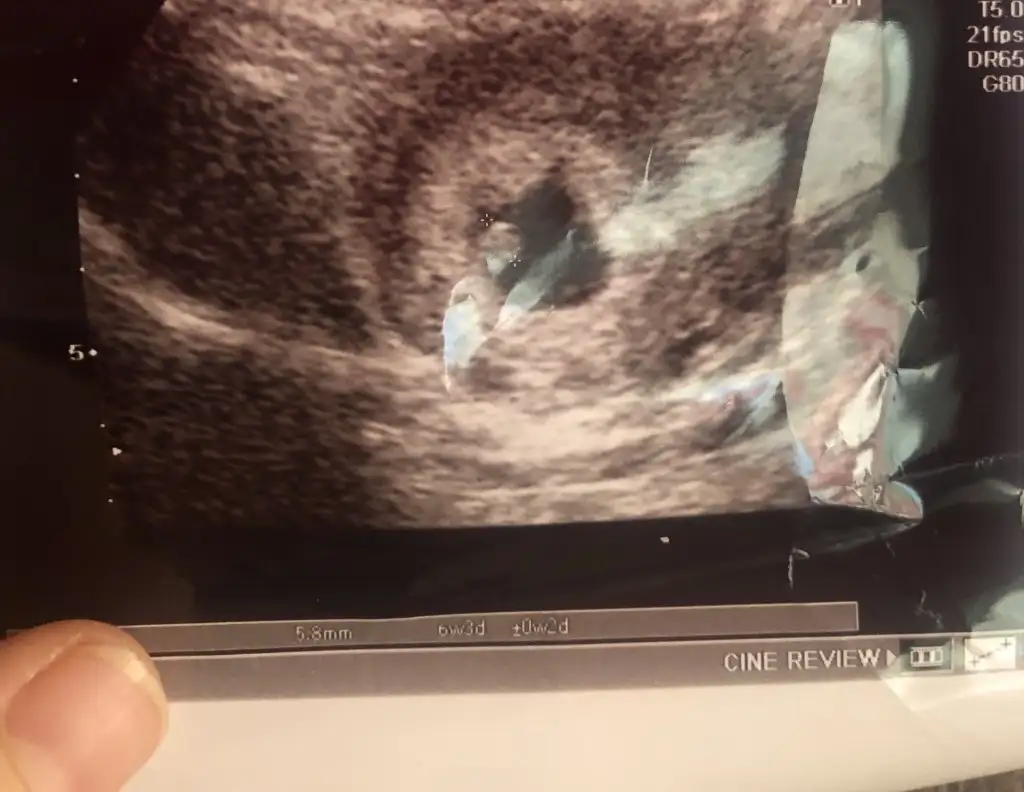

Ben de yorum istiyorum kızlarrr ilk fotoğraf ilk diğeri de 6+3 ultrason